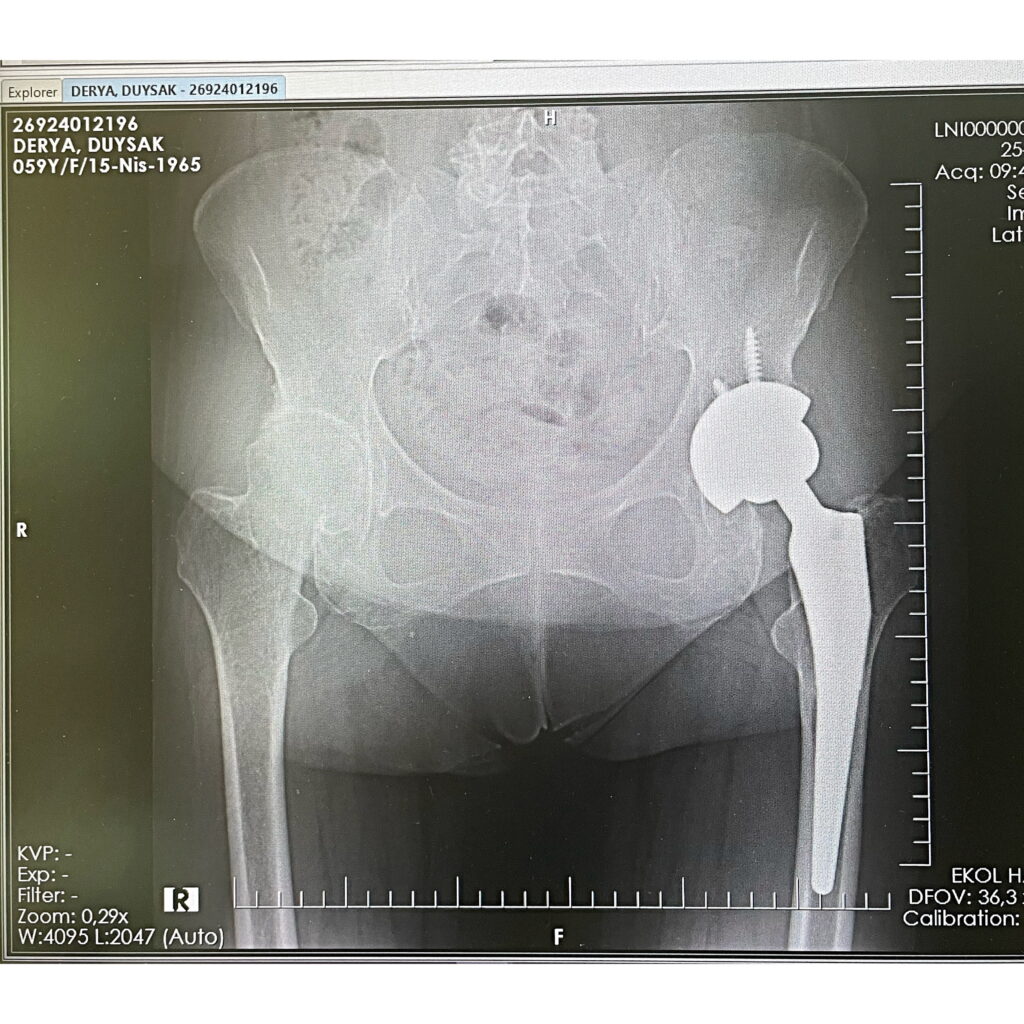

D.D.